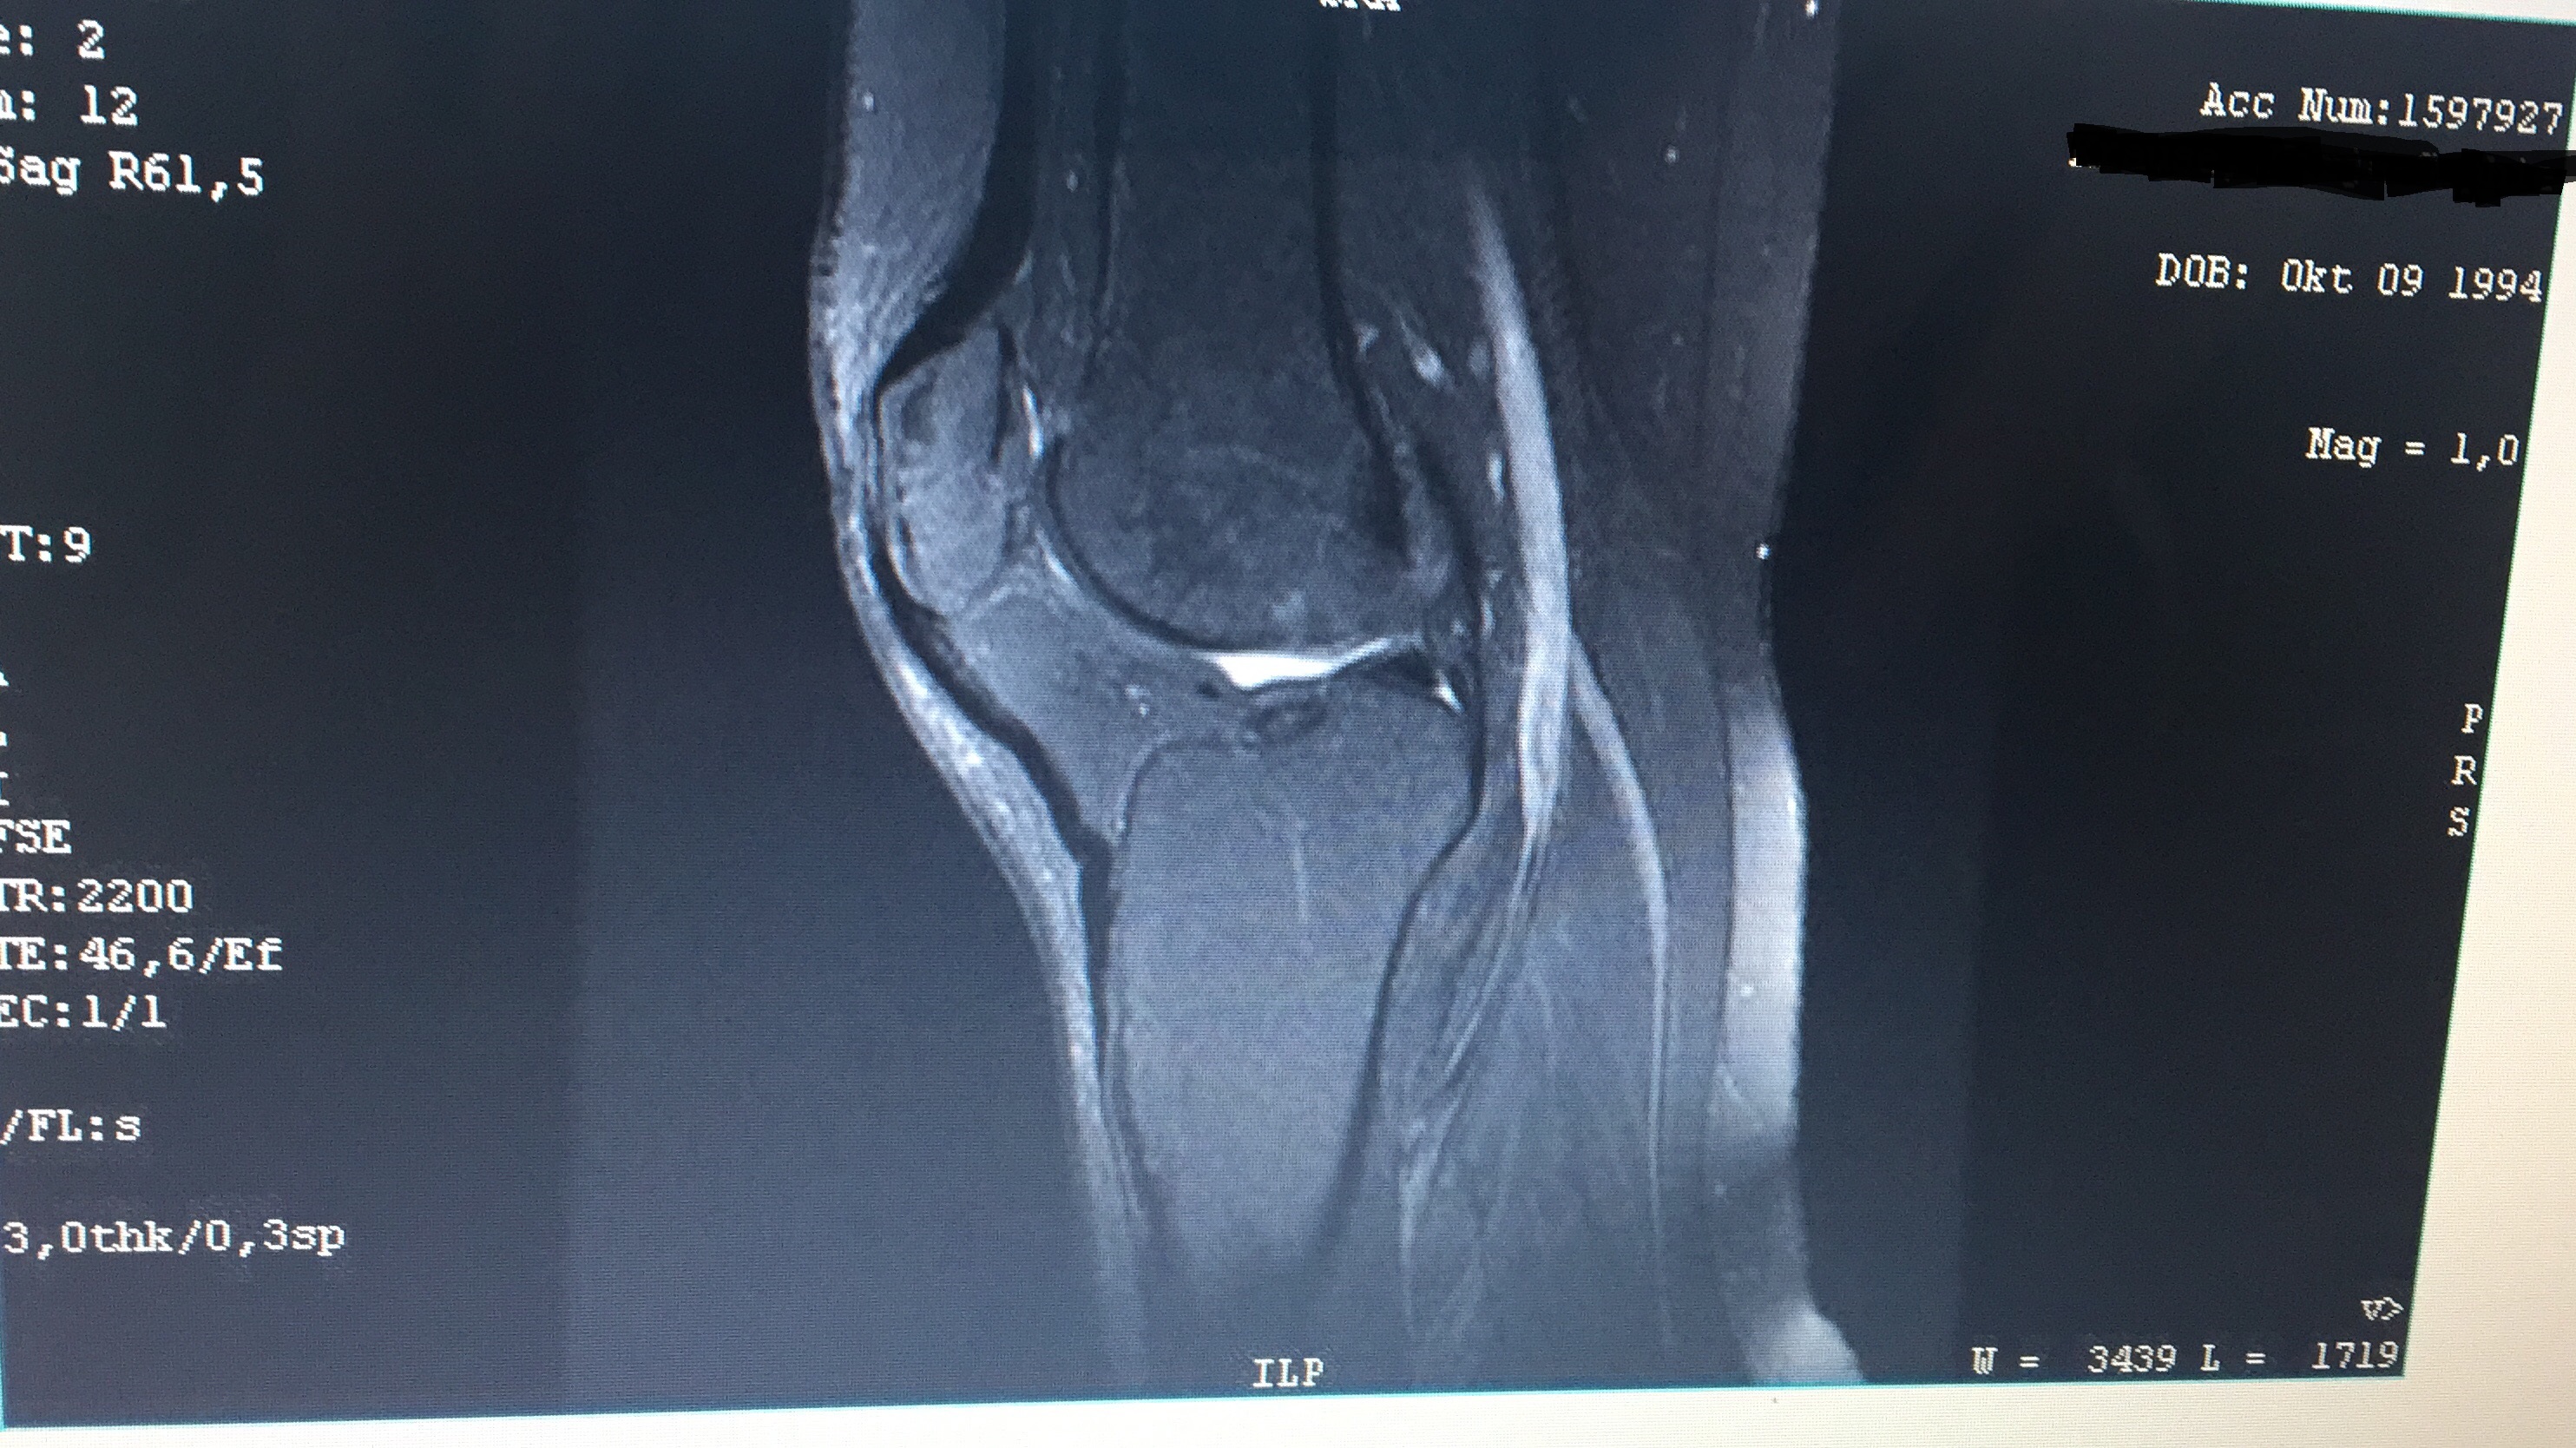

Knie MRT weiß im Gelenk? siehe Bild? (Gesundheit und Medizin, Sport und Fitness)